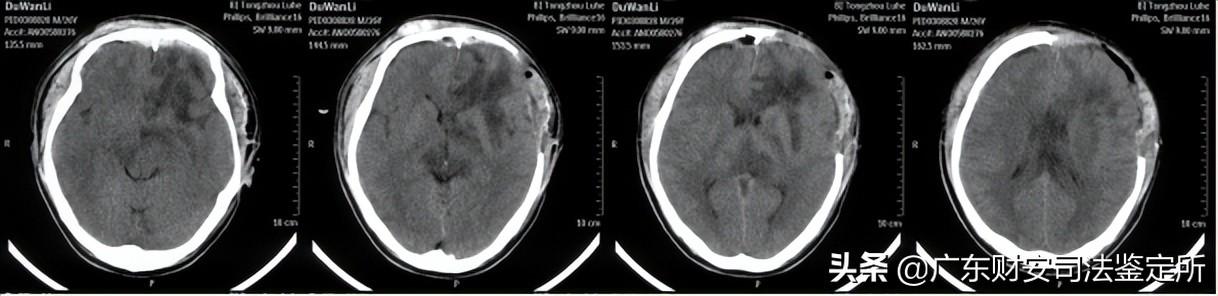

2014-6-16颅面部CT片示:双侧额骨、双眼眶壁、双侧鼻骨等颅面骨多发骨折,颅底骨折,左侧开颅术后,左侧额颞顶部分颅骨缺损,局部脑组织稍向外膨隆,颅内积气,双侧额叶可见少量高密度影,右侧额部可见金属探头,左侧额叶可见不规则大片状低密度区,左侧侧脑室稍受压,局部中线结构稍右偏。(见附件5-A)

2014-6-24颅脑CT片示:右侧额部金属探头已拔除,左侧脑室受压解除,中线结构居中,余基本同前。(见附件5-B)

2014-8-5首次术后颅脑CT片示:左侧开颅术后,额颞部分颅骨缺损,双侧额叶、左侧基底节区、侧脑室旁均可见软化灶、形态不规则,左侧侧脑室轻度扩张,中线结构居中。(见附件5-C)

2014-9-18修补术后复查颅脑CT片示:左侧额颞部颅骨减压修补术后,胼胝体、左侧基底节区可见斑片状低密度灶,双侧额叶可见不规则低密度灶,中线结构居中。(见附件5-D)